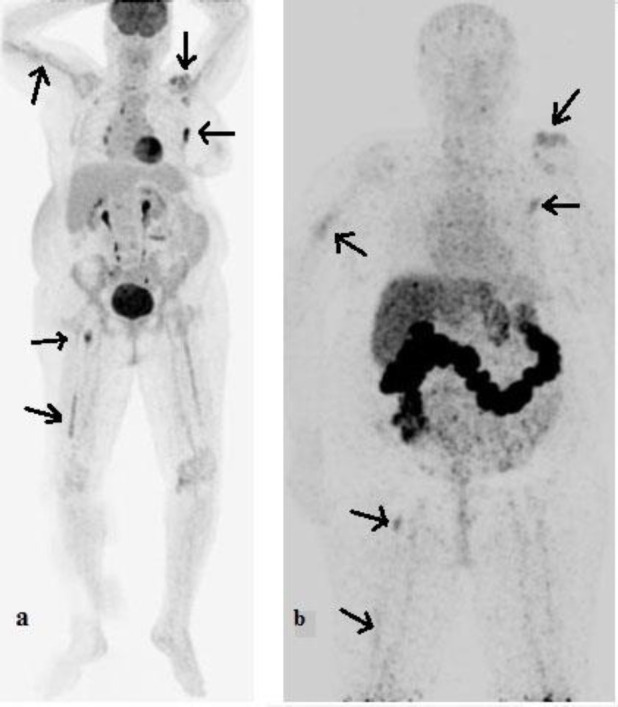

The image of tumor-bearing mice at 24 and 72 h after intravenous injection is indicated in Figure 3. Also, PET/CT images after injection of

Figure 3.

PET images of [89Zr]Zr-Trastuzumab in tumor-bearing mice at 24 and 72 h post-injection

[18F]FDG and [89Zr]Zr-Trastuzumab to a woman with HER2-positive metastatic breast cancer that was under treatment with Herceptin have been demonstrated in Figure 4.

Figure 4.

PET/CT images of a woman with HER2-positive metastatic breast cancer after injection of [18F]FDG (a) and [89Zr]Zr-Trastuzumab [96 h (b)]

[89Zr]Zr-Trastuzumab PET/CT demonstrated [89Zr]Zr-Trastuzumab-avid skeletal and right lung metastatic lesions, which were shown previously by [18F]FDG PET/CT findings. The [18F]FDG PET/CT scan had higher quality images. Still, the notable advantage of [89Zr]Zr-Trastuzumab PET/CT is delineating HER2+ metastasis, which is unique and could be significant in the diagnosis of HER2+ malignancies and HER2 based treatments.